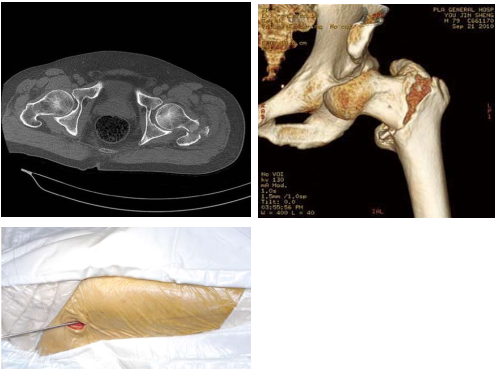

二 股骨粗隆间骨折的治疗首选股骨近端髓内钉固定(PFNA/Intertan)

髓内固定属于中心性固定不需要对内侧骨块解剖复位固定,不干预内侧的生物学环境,自然增加了骨折的愈合率。因此,髓内固定适于任何类型的骨折固定,特别是在不稳定型骨

折固定中表现优异。

三 股骨粗隆间骨折人工股骨头置换术

■ 手术适应证:股骨粗隆间骨折多采取内固定的方式治疗,行人工关节置换需严格把握适应证。